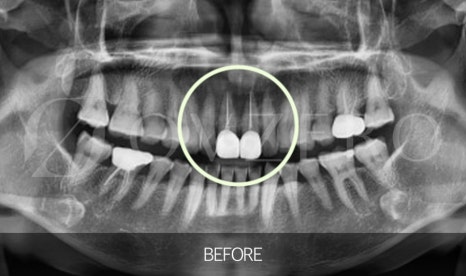

충치가 깊어지거나,

치아가 깨지거나,

강한 힘이 반복적으로 가해지면

이 신경까지 염증이 번질 수 있습니다.

이 상태에서는

겉으로 보이는 충치만 제거해서는 해결되지 않고,

염증이 생긴 신경을 제거한 뒤

치아 안쪽을 깨끗하게 정리하는 치료가 필요합니다.

이게 바로 우리가 흔히 말하는 신경치료입니다.